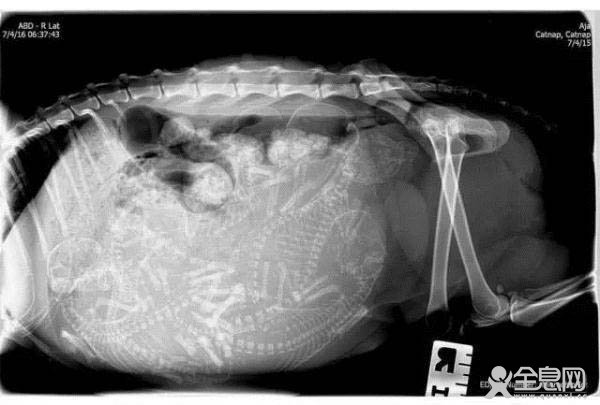

怀孕的猫。

猫妈妈换了个姿势。换个角度看猫宝宝……好挤……